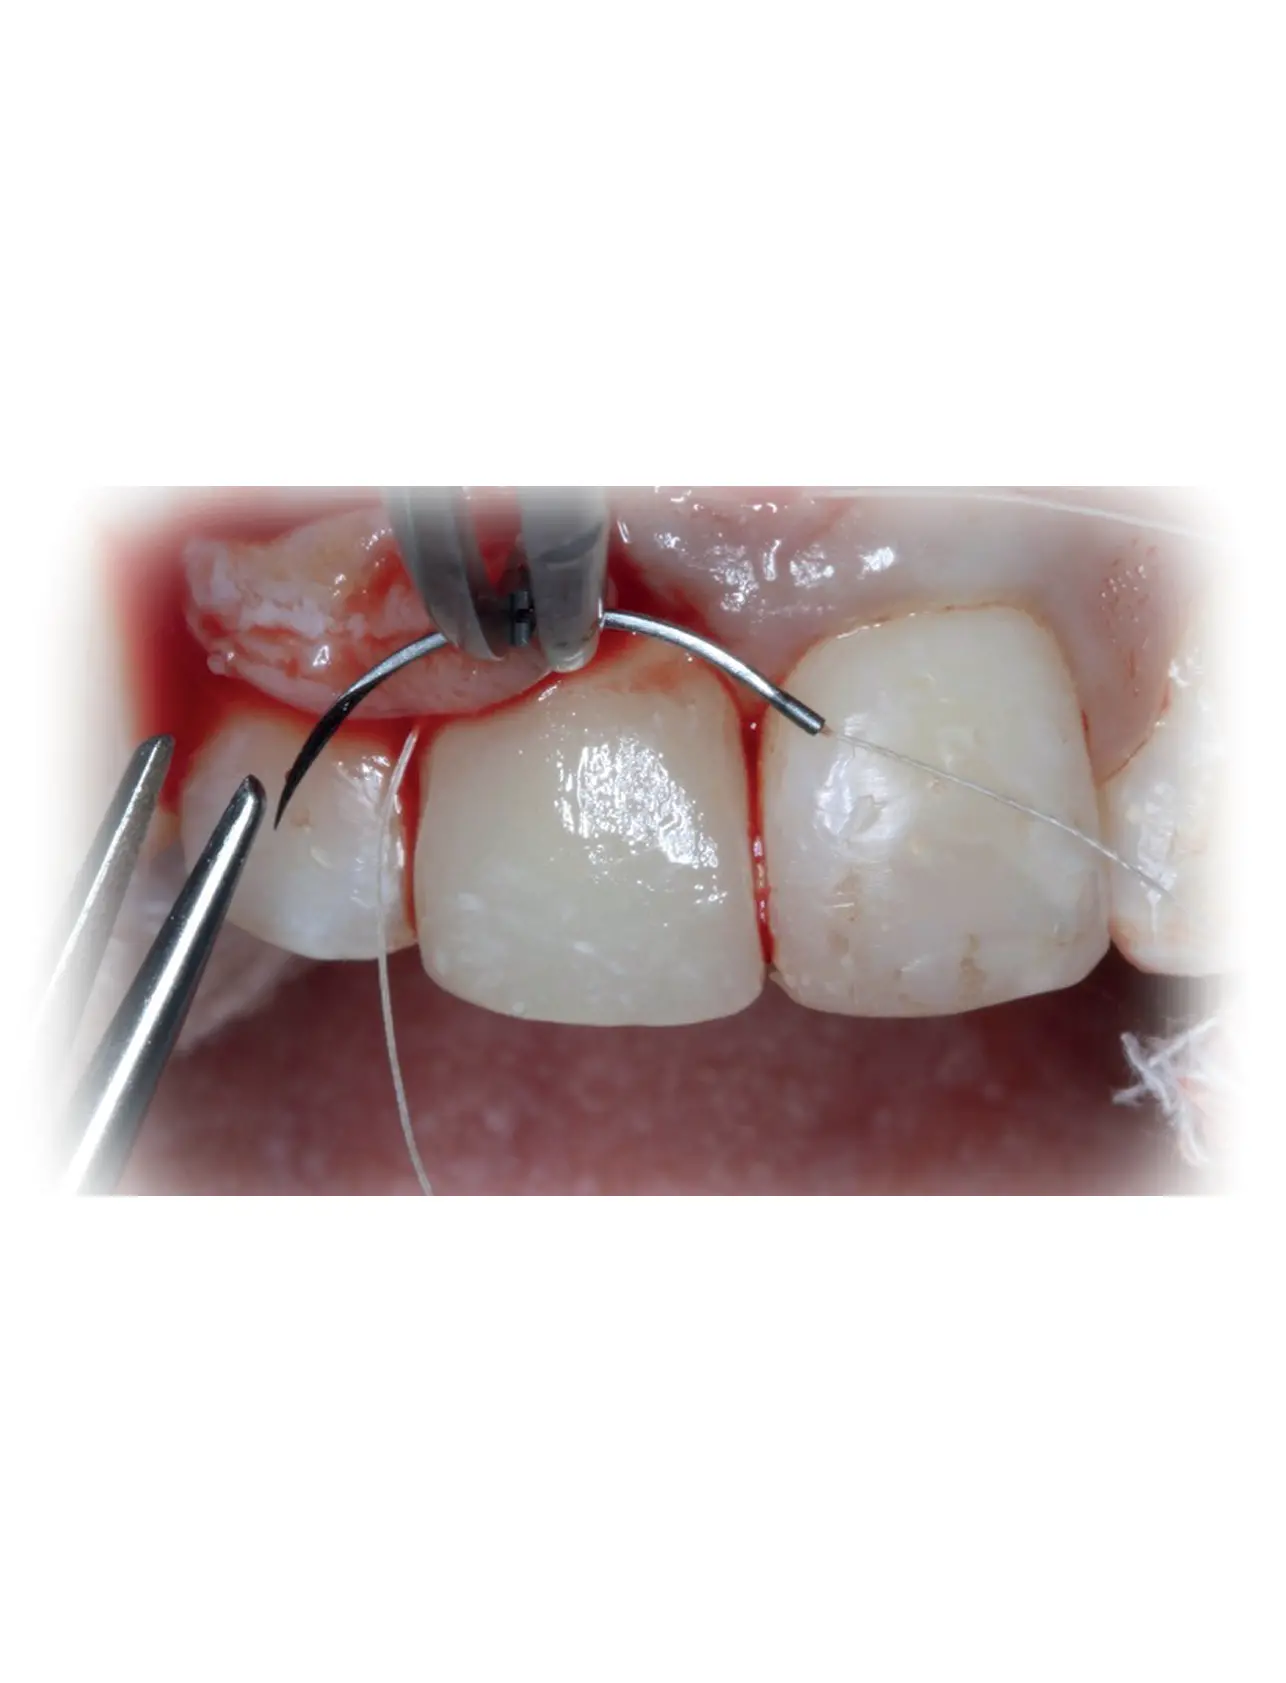

PERIODONTAL FLAPS & SUTURING TECHNIQUES & PRINCIPLES

Medical suturing is a crucial aspect of surgical medicine, used to close wounds after surgical procedures and repair tissue injuries to accelerate the healing process. The principles of medical suturing involve the use of specialized tools such as surgical needles and sutures.

- Suturing Techniques:

- Various suturing techniques are used in surgery, such as:

- Simple Interrupted Stitch

- Mattress Stitch

- Skin Stitch

- Fine Tissue Stitch

Suturing Instruments:

- Surgical Forceps:

- Used to hold tissues and sutures.

- Surgical Needles:

- Available in different sizes to match the wound type.